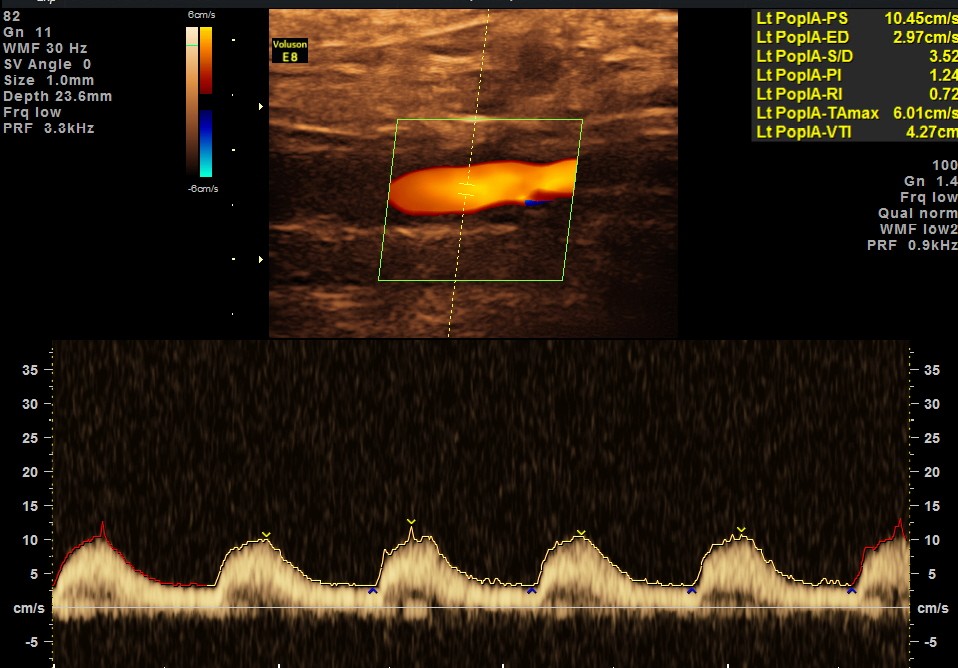

EXTENSIVE ATHEROSCLEROTIC OBSTRUCTIVE DISEASE OF THE LOWER LIMB ARTERIES WAS SEEN WITH THE CHANGES IN THE RIGHT COMMON FEMORAL ARTERY BEING MORE THAN THE LEFT CFA.